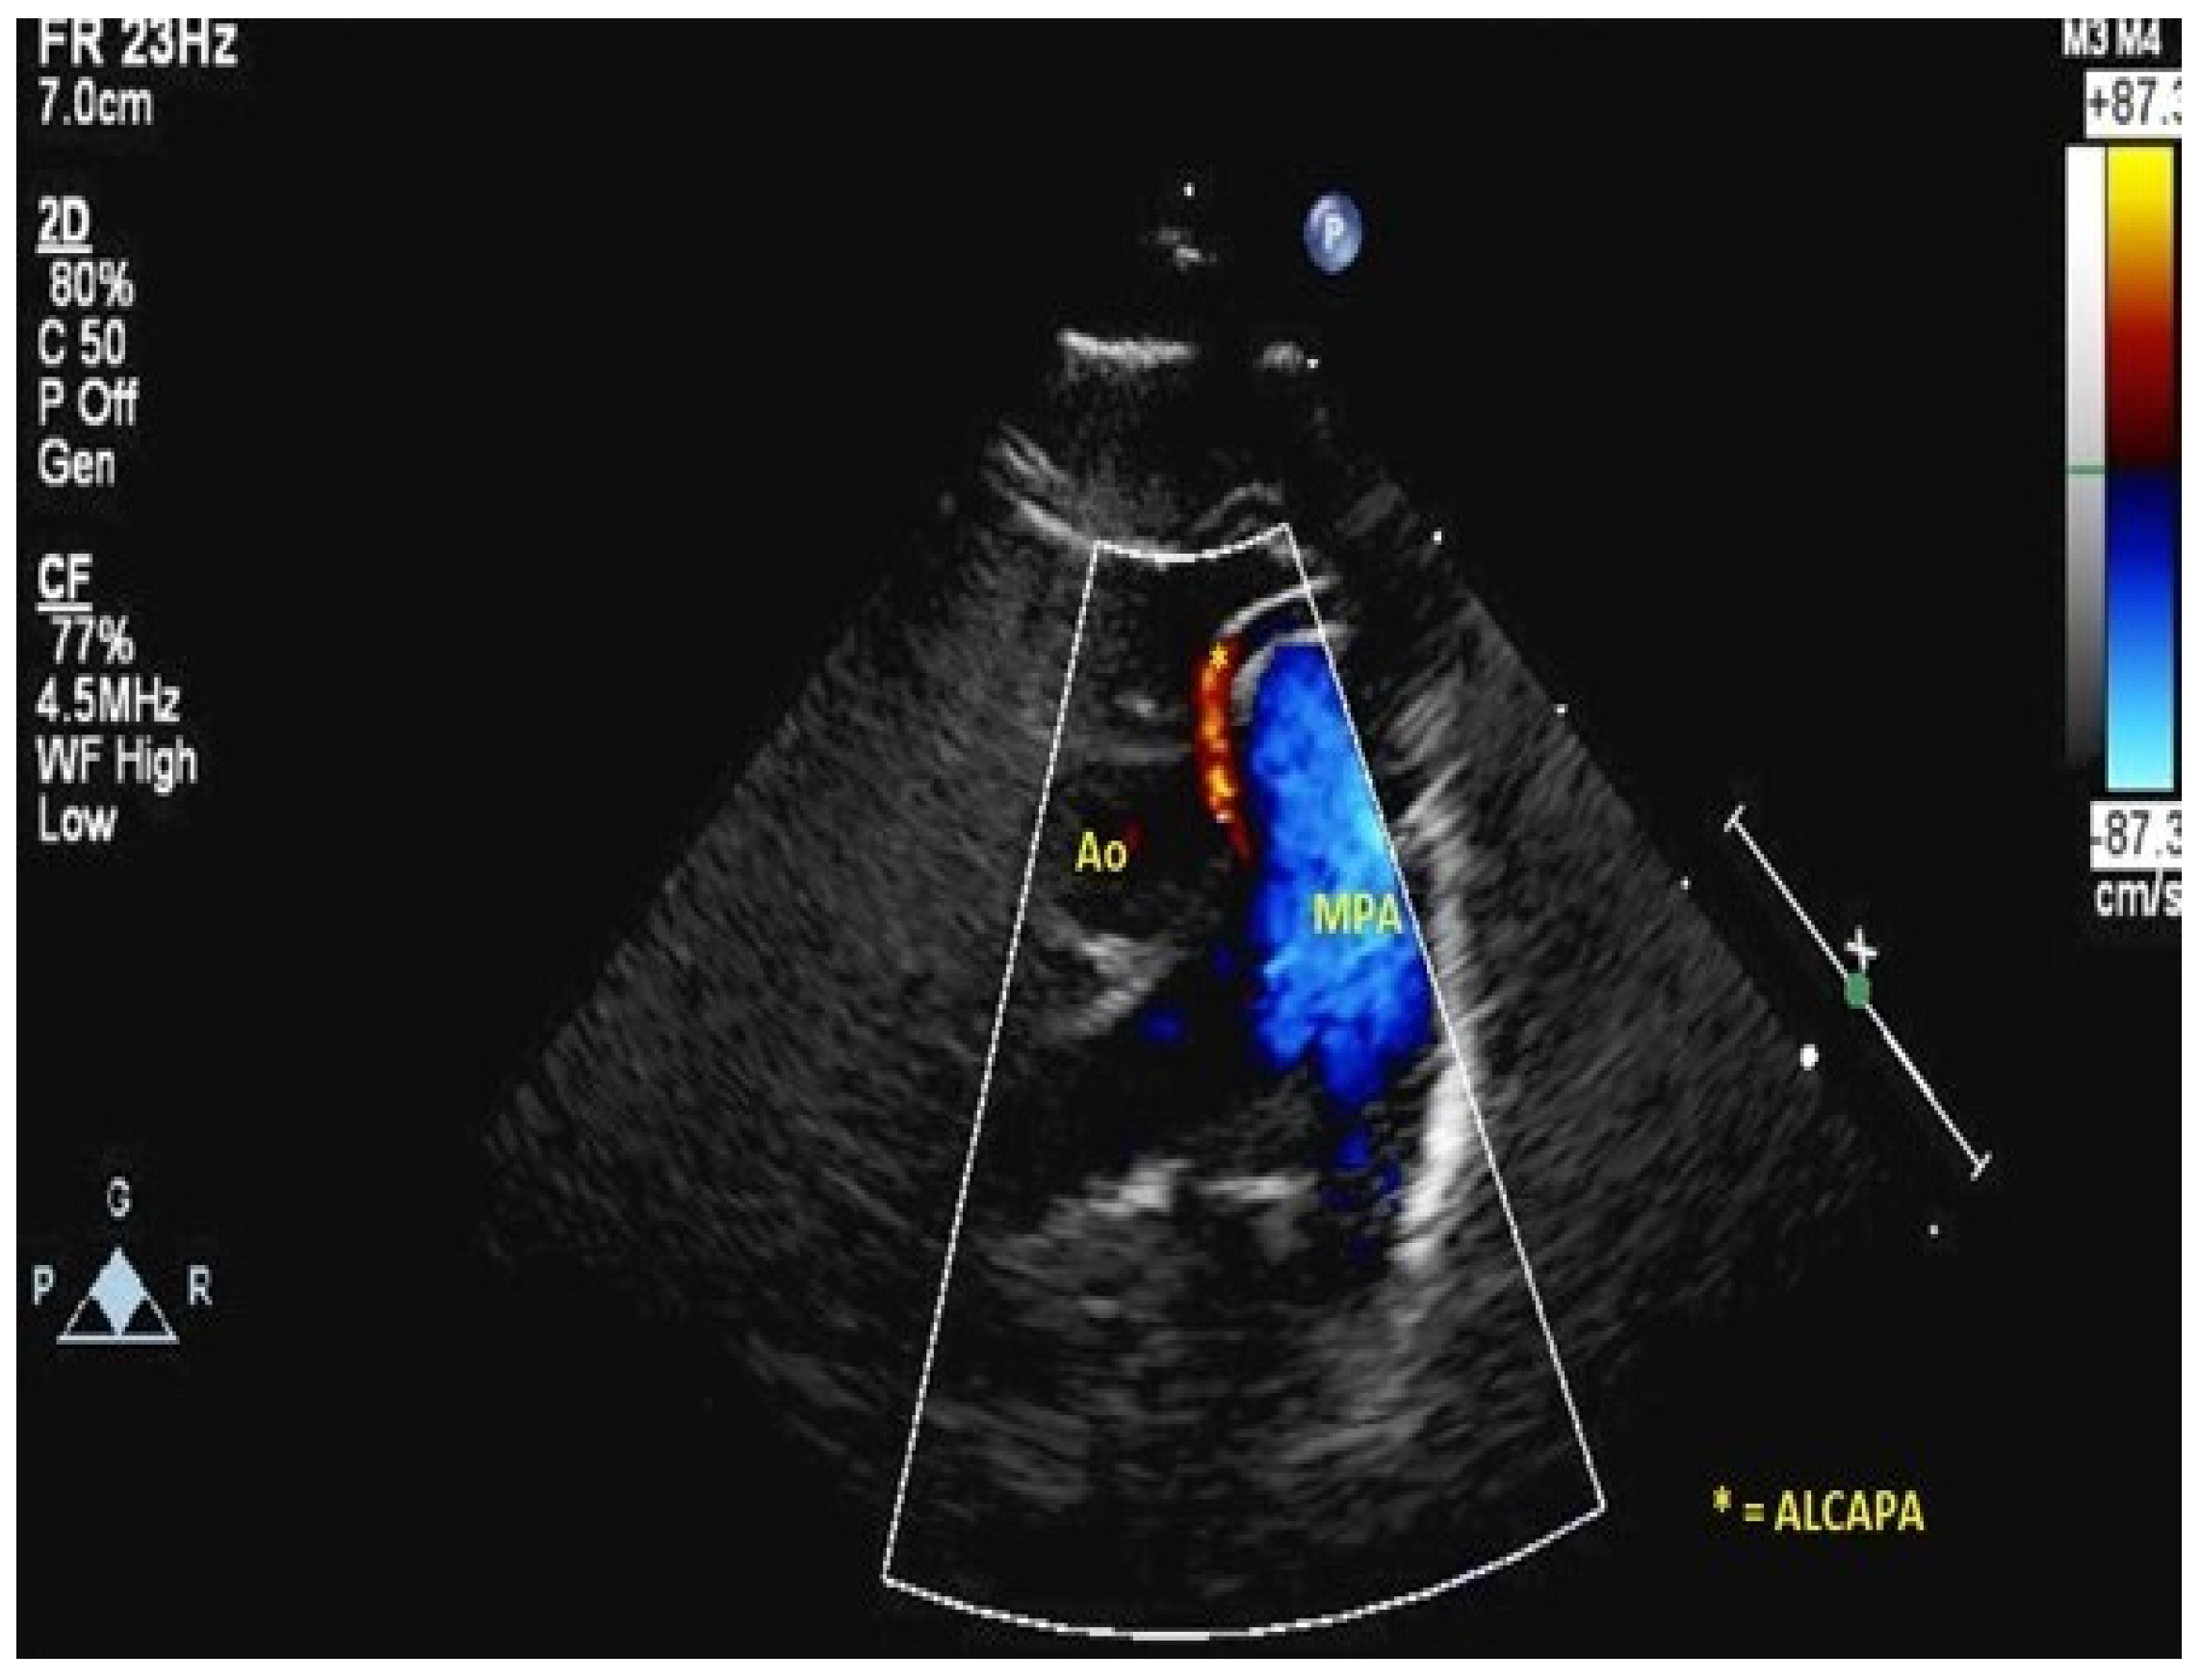

| ALCAPA | anomalous left coronary artery from the pulmonary artery |

- Frommelt, M.A.; Miller, W.; Williamson, J.; Bergstrom, S. Detection of septal coronary collaterals by color flow Doppler imaging is a marker for anomalous origin of a coronary artery from the pulmonary artery. J. Am. Soc. Echocardiogr. 2002, 15, 259–263. [Google Scholar] [CrossRef]

- Patel, S.G.; Frommelt, M.A.; Frommelt, P.C.; Kutty, S.; Cramer, J.W. Echocardiographic diagnosis, surgical treatment, and outcomes of anomalous left coronary artery from the pulmonary artery. J. Am. Soc. Echocardiogr. 2017, 30, 896–903. [Google Scholar] [CrossRef]